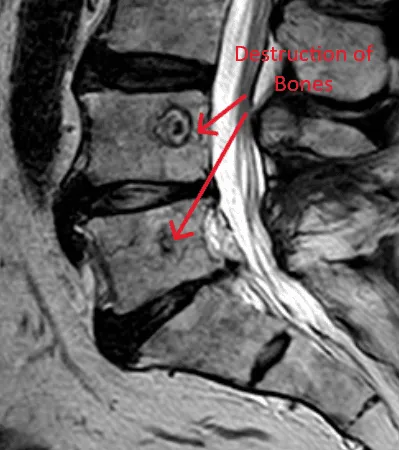

MRI image showing spinal bone destruction, highlighted by red arrows and text.

Destroys Normal Bone & Bone Marrow

MRI of the lower spine highlighting bone necrosis with red arrows.

Bone Necrosis (Bone Death)